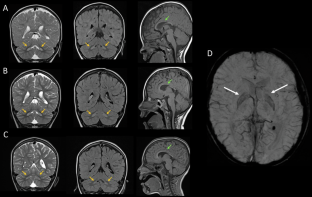

Pathogenic WDR45 variants cause neurodevelopmental disorders (NDDs) including β-propeller protein-associated neurodegeneration (BPAN), characterized by developmental delay (DD), ataxia and extrapyramidal signs. Our patient, initially presenting at 22 months with DD, now, aged 7, shows intellectual disability, ataxia and rigidity. MRI findings were suggestive of Leigh syndrome, a mitochondrial disorder (MD) phenotype, with no brain iron accumulation. Reduced activity of respiratory chain complex I (cI) and complex II (cII) was identified in muscle and fibroblasts, and a cII reduction in muscle only; however, a primary MD was excluded. Exome sequencing revealed a de novo pathogenic WDR45 variant. Autophagic flux analysis showed a mildly reduced p62 response, with normal autophagy progression. This is the first report linking WDR45 to cI assembly and activity, indicating mitochondrial dysfunction as a potential pathophysiological BPAN mechanism. We recommend considering WDR45-related NDDs when diagnosing early-onset NDDs, particularly Leigh-like encephalopathies with cI deficiency, even without brain iron accumulation.